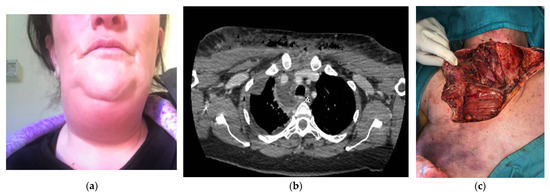

Out of the 18 patients, 17 underwent surgery during the first 12 h from admission to the E.R. and one on the first day. One patient was operated after 6 days from the first admission in another hospital: she was a 48 years old woman who had a dental extraction ten days before and that noticed cervical swelling and odynophagia (Figure 1). After one week of oral antibiotic intake without benefit, she was admitted to a general hospital for fever and cervical pain. An ultrasound showed only edema of the cervical fascial layers; for this reason, she started intravenous antibiotic therapy, but after 6 days, she had spontaneous drainage of pus from the neck. Then she was referred to our hospital and immediately operated (she underwent two cervicotomies and three right thoracotomies, along with vacuum-assisted closure therapy because of cervico-thoracic deep infection).

Figure 1.

(a) A 48-year-old woman with cervical swelling and odynophagia. (b) A preoperative computed tomography scan showing the spread of infection extending to the lower anterior mediastinum, below the tracheal bifurcation with associated right pleural effusion. (c) Ample cervicotomy extended to the anterior pectoral exposition for a cervico-thoracic deep infection.